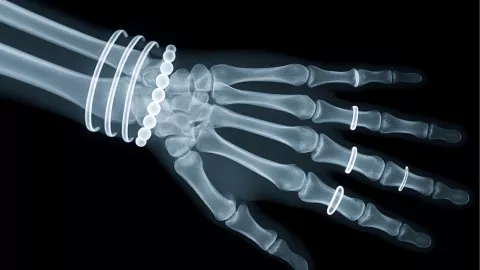

Tener un anillo atorado puede causar preocupación, especialmente cuando el dedo está inflamado o sensible. Sin embargo, antes de entrar en pánico, existen varias técnicas simples y caseras que pueden ayudarte a retirarlo sin dolor.

- Si notas que el dedo está muy inflamado, amoratado o adormecido, lo mejor es acudir a recibir atención médica.